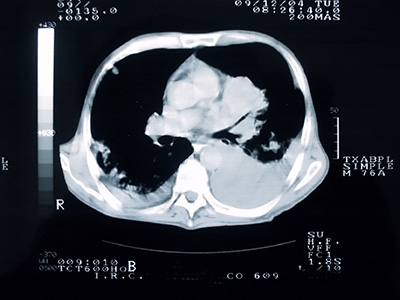

Applying computational and functional techniques that employ physiologic imaging and advanced image processing to correlate imaging characteristics with molecular features of cancer